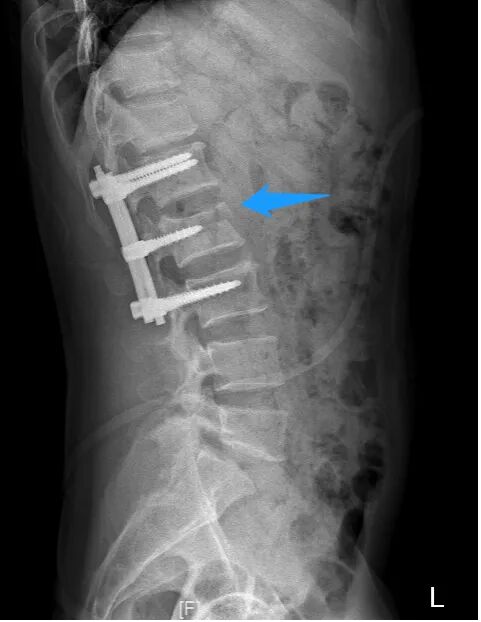

手术后当天,姚某右下肢已可轻微活动,经过1月余的专科康复后,姚某已可拄拐下地站立。他激动地说,“我以为自己将永远躺在床上了,想不到医生还能让我站起来,非常感谢医护人员高超技术和精心照顾。” 腰椎术前X线侧位片 术前磁共振 术前磁共振显示神经明显受压 姚某术后恢复情况 薛厚军副主任医师指出,脊柱骨折是临床常见脊柱损伤,发病群体是青壮年,指的是因外力对脊柱骨质造成连续性的破坏、高处坠落、车祸等高能量损伤是导致脊柱骨折的主要原因。对于严重的脊柱爆裂性骨折,可以造成脊髓或神经的损伤,导致肢体运动感觉障碍或者瘫痪,严重影响病人的生存及生活质量。所以,只要条件允许,应尽早手术治疗。 随着科技的进步以及人们自我保护意识的提高,近年来脊柱骨折的病人已有所减少,但对于其引起的严重后果我们仍不能忽视。建议广大民众出现脊柱骨折后要就近在有实力的医院诊治,搬动要严格轴线平抬,避免二次伤害,以免延误病情。